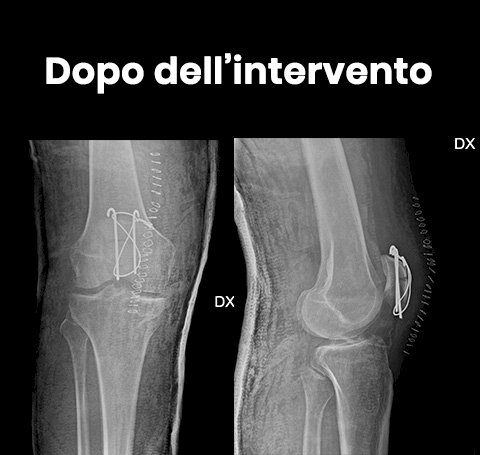

Se la frattura è scomposta ovvero i frammenti ossei si sono spostati facendo perdere l'anatomia normale della rotula sarà necessario intervenire chirurgicamente per ridurre la frattura quanto più anatomica possibile e fissarla in modo che non si scomponga durante il periodo della guarigione dell'osso. Infatti i tendini che si inseriscono sulla rotula potrebbero scomporre la frattura trazionandone i frammenti durante il movimento del ginocchio, quindi è necessario fissarla con dei mezzi di sintesi una volta ridotta mediante cerchiaggi metallici, viti o fili metallici.